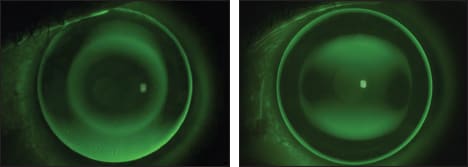

Figure 1. Fluorescein patterns showing the different alignment of a spherical ESA (left) and the dual-toric ESA (right).

The lenses were manufactured in a fluorosilicone acrylate material (Boston XO, Bausch + Lomb), Dk 100, for overnight wear. Figure 1a shows the fluorescein pattern of a spherical ortho-k ESA lens on this patient, and Figure 1b shows the same eye with the dual-toric design.